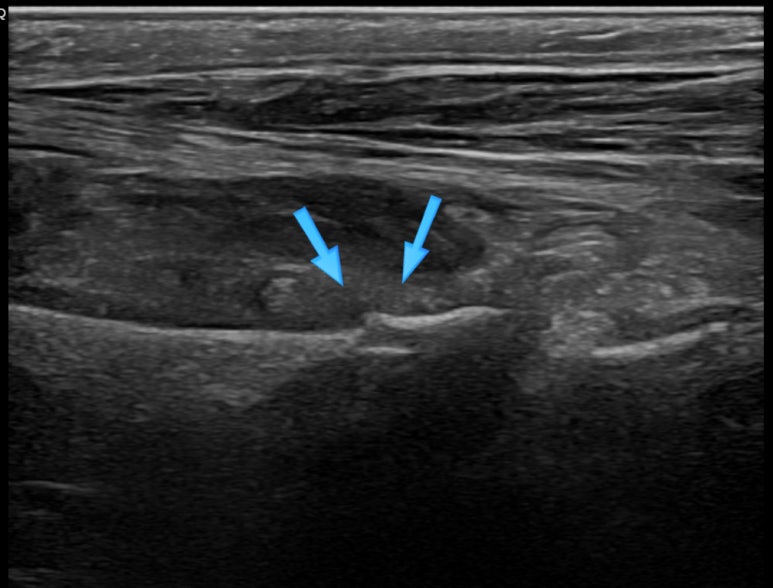

한의학적으로 어혈/담음증에 해당하여 경혈초음파를 시행했습니다.** > 경혈 초음파 등 뿐만 아니라 발바닥쪽 통증도 호소하셔서 족소음신경 용천혈(溶泉穴) 주변을 초음파로 관찰한 영상입니다.**

용천혈 주변 좌측 / 우측

좌측의 정상 뼈 모습**은 표준 경혈 초음파 영상과 동일한데요.

우측 용천혈의 아래쪽에서 연속되어야 할 뼈가 끊어져보입니다.

뼈(骨)가 끊어져 보인다(折)는 것은 말 그대로 골절(骨折)을 의미합니다. 한의학 고전 중 외대비요에서 처음으로 골절이라는 병명을 언급하였고, 의종금감에 이르러 골절에 대한 체계가 잡히게 되었습니다. 현대 한의학의 외과 영역에서 골절은 주요 질환으로 치료하고 있는데요. 하지만 과거의 골절됐던 부분이나 퇴행성 변화로 뼈가 울퉁불퉁한 부위는 경혈 초음파상 뼈(骨)가 끊겨 보일 수 있고요.

무엇보다 경혈 초음파가 "골절"의 골든 스탠다드 진단법이 아니기 때문에 이번에 발생한 급성 골절이라고 확정지어 진단내릴 수 없는 경우가 많습니다.

그래서 골절인지 아닌지 정확한 감별하기 위해 640 CT가 가능한 협력병원으로 X-ray와 CT 검사를 의뢰하였습니다.